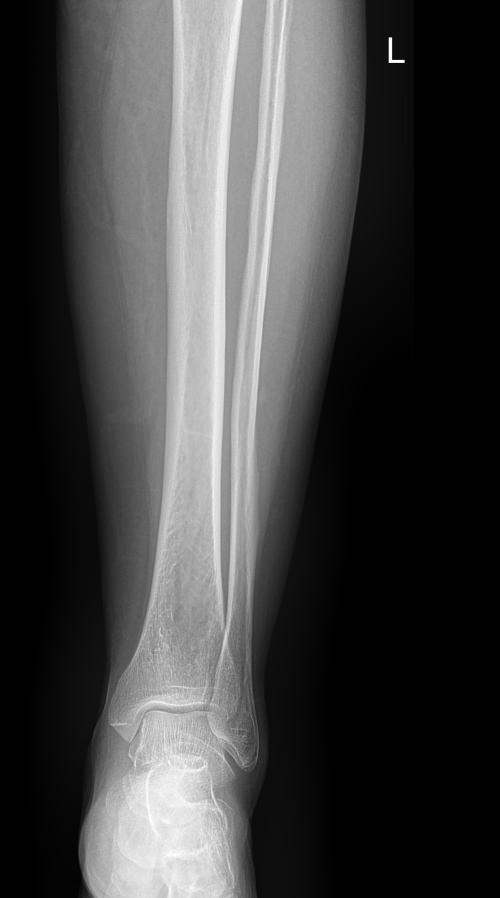

В области голени располагаются 2 кости ― большая и малая берцовые. Разные по толщине, они, тем не менее, составляют крепкую конструкцию, позволяющую человеку ходить и бегать, нести вес тела и дополнительный груз. Повреждение и травмы голени, а также прилежащих суставов, коленного и голеностопного, резко уменьшает мобильность человека. Хронические процессы, начинаясь незаметно, постепенно приводят к тому же.

Рентген является простым, доступным, высокоинформативным и безболезненным видом диагностики патологий костной ткани, в том числе ― костей голени. А современная цифровая аппаратура позволяет выполнять снимки настолько часто, насколько этого требует заболевание, не превышая допустимую дозу облучения.

На снимке рентгенолог последовательно просматривает все образования голени и описывает их изменения:

• Новообразования: местоположения, затрагивают ли костную ткань;

• Диафизы и эпифизы костей: наличие перелома, его смещения, костной мозоли, их месторасположение и соответствие срокам травмы;

• Костная ткань: очаги разрежения, уплотнения, размягчения, склерозирования и других изменений, в том числе послеоперационных;

• Надкостница: истончение, обызвествление;

• Входящий в снимок сустав: есть ли изменения, типичные для травмы или воспаления;

• Мягкие ткани: есть ли отек и инородные тела.